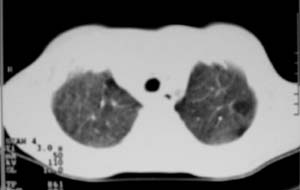

以下是引用zjzjr在2007-9-20 12:29:00的发言:[br]双肺磨玻璃改变,考虑肺水肿.

以下是引用yangzongshan在2007-9-20 18:29:00的发言:[br]两肺毛玻璃样改变,其内可见肺纹理影,无胸腔积液,故考虑肺泡蛋白沉积症

以下是引用276894491在2007-9-20 13:40:00的发言:[br]考虑肺水肿;外源性过敏性肺炎不排除。

以下是引用逸风在2007-9-20 20:45:00的发言:[br]两肺磨玻璃样改变,临床病史短,发热,考虑病毒感染合并右肺代偿性肺气肿.待排肺水肿,病史短,不支持肺泡蛋白沉着症.